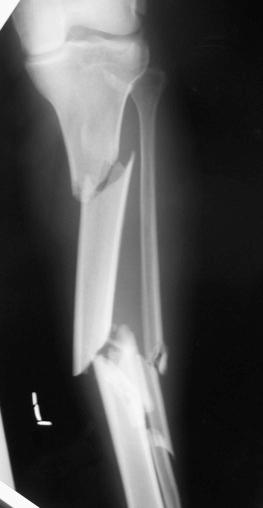

Any condition increasing the content or reducing the volume of a compartment could lead to compartment syndrome, but the most prevalent cause of compartment syndrome is trauma associated with a fracture. In the cases of fracture, energy from the trauma is dissipated into the bone and muscle, inducing intracellular swelling at the site of the trauma. The fracture site is also susceptible to hematoma after the injury, further amplifying the problem by increasing the volume and, therefore, the pressure of the compartment. High-energy tibial fractures are the most common type of injury associated with compartment syndrome, more specifically, bicondylar plateau fractures and segmental or comminuted tibial shaft fractures ( Figs. 17.2 and 17.3 ). ACS has been reported to complicate tibia fractures in as few as 1% to 9% of all cases and as high as 24% of polytrauma patients. However, it is important to consider that compartment syndrome can also develop secondary to arterial injury, occlusions, reperfusion injury, crush injuries, prolonged malposition, burns, electrocutions, snake venom, stressful athletic activity, contusions, and infiltrations from intravenous (IV) sites. There is also the potential for a compartment syndrome to arise from postresuscitation systemic inflammatory response syndrome after massive blood and fluid resuscitation.

Fig. 17.3, This radiograph shows a segmental tibial shaft and fibula fracture. This type of high-energy injury has a high risk of developing acute compartment syndrome.